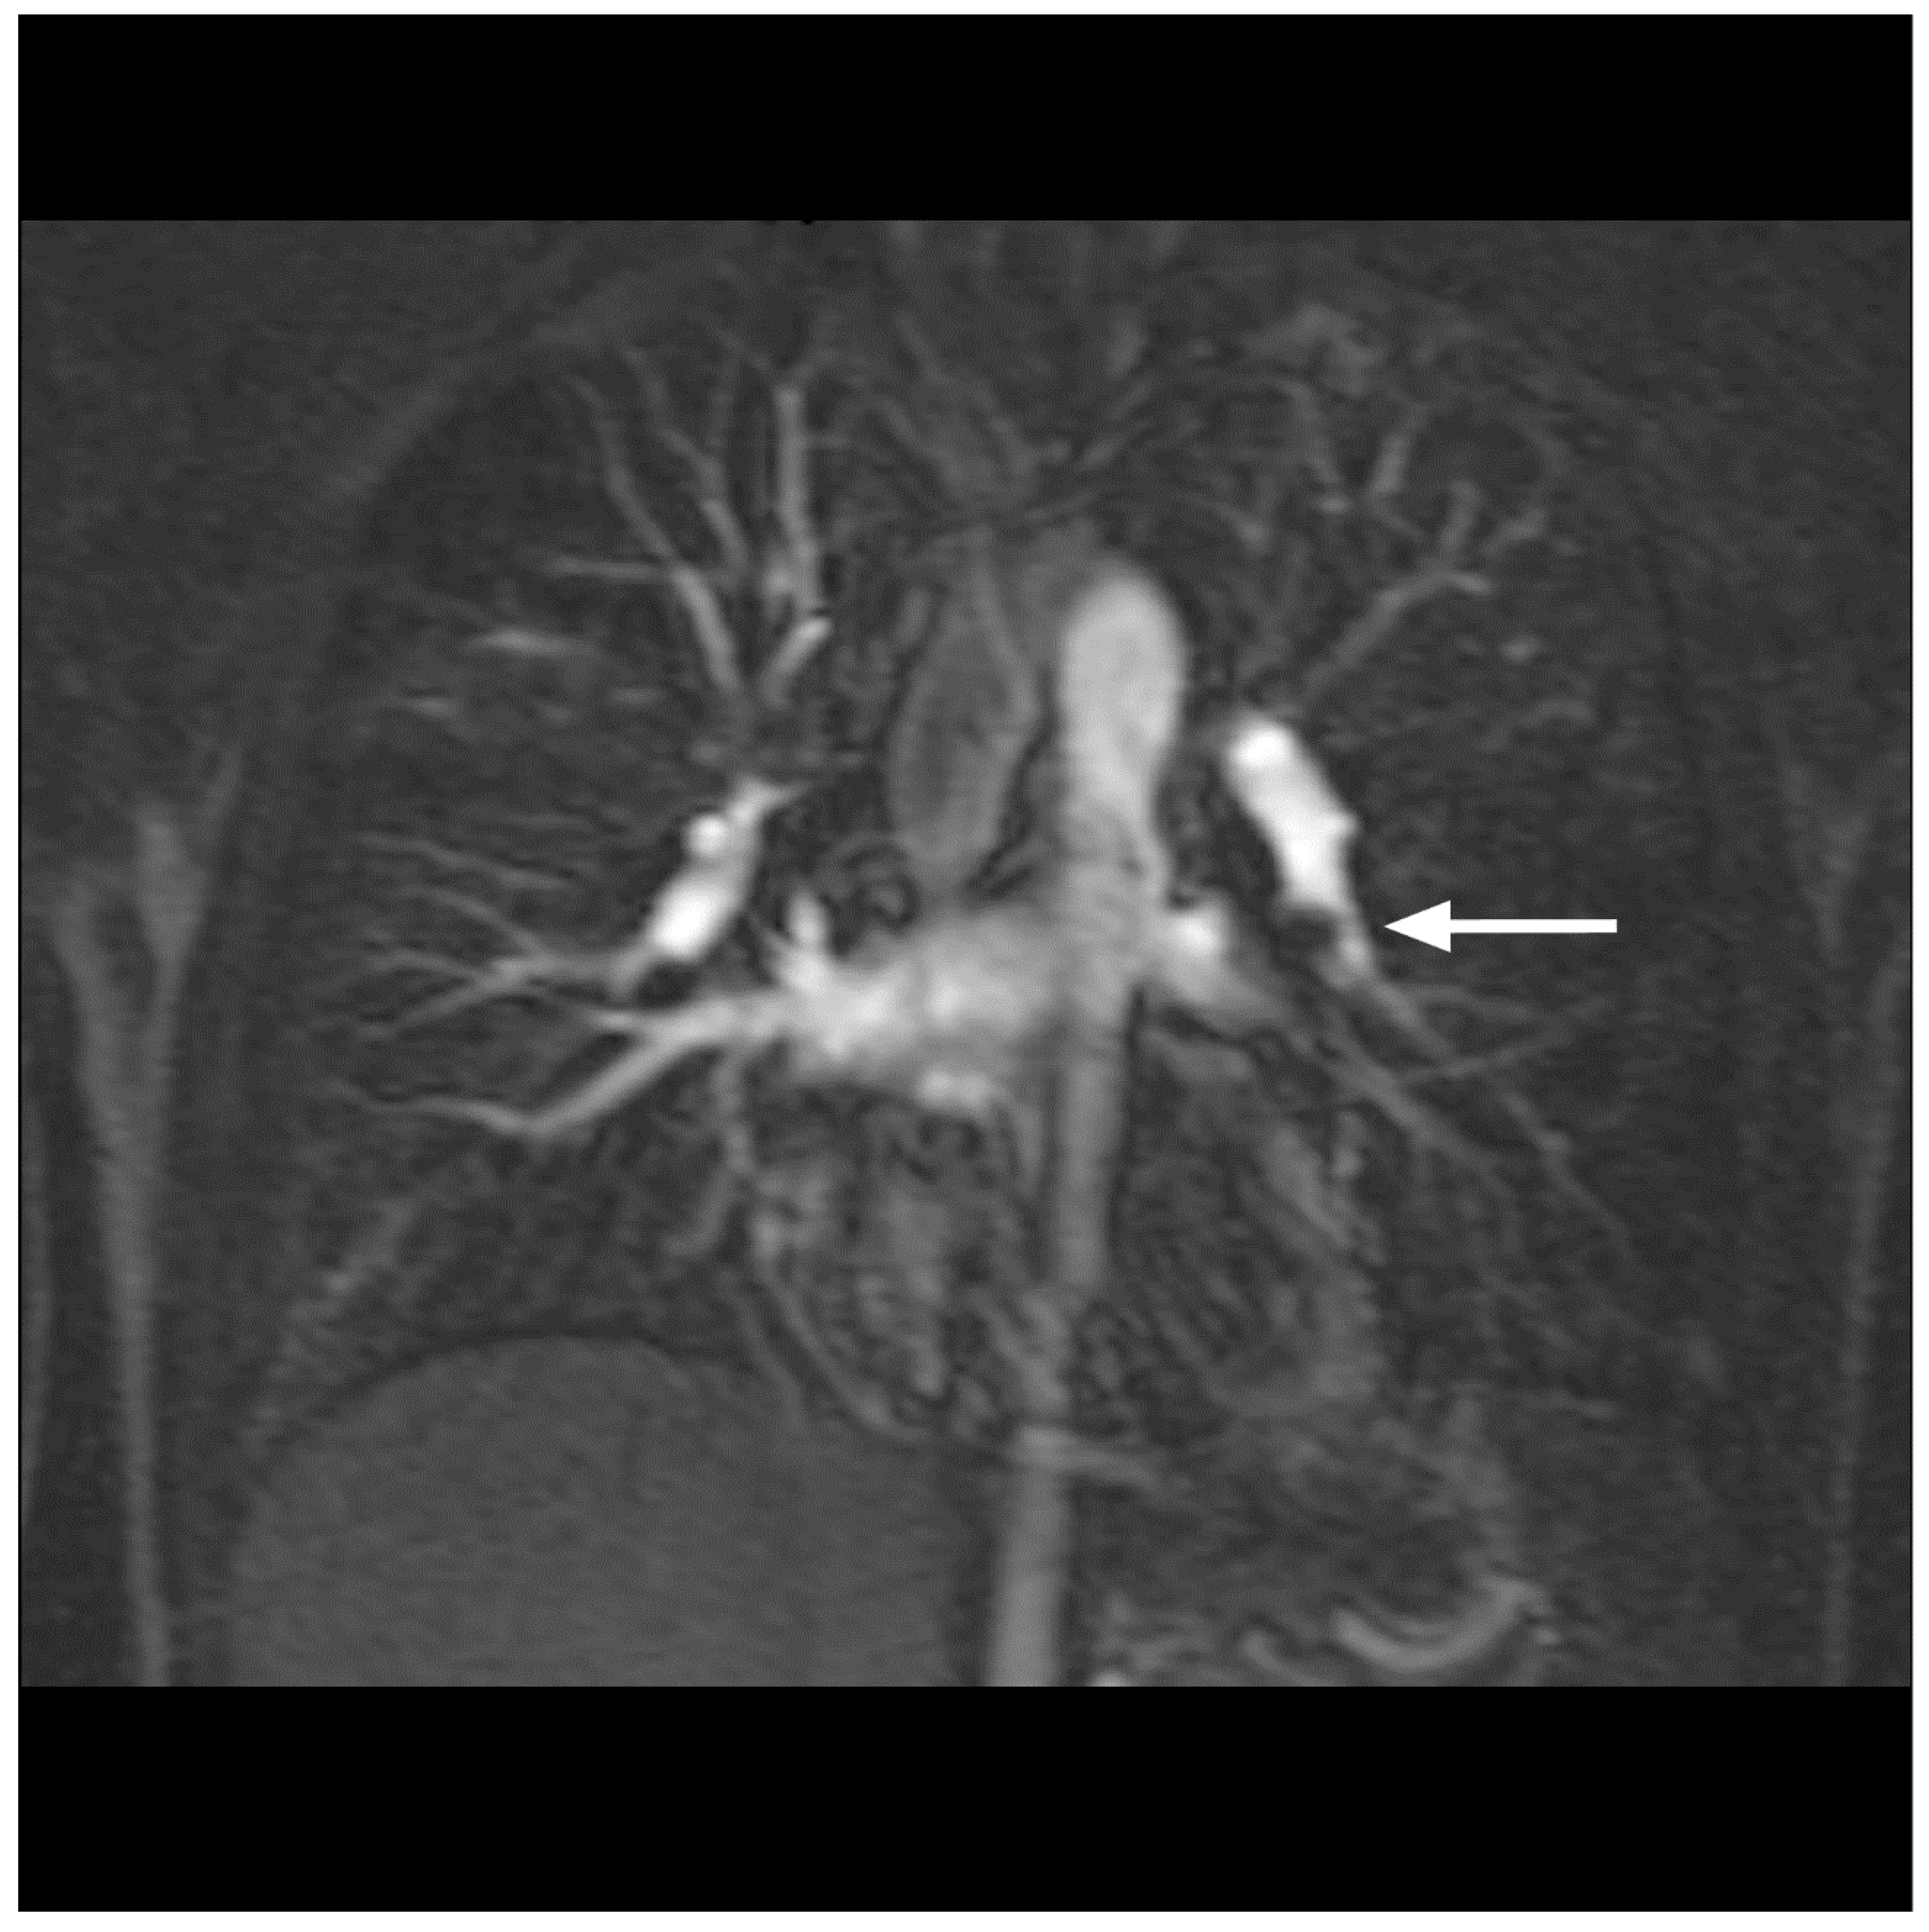

- Hansch, A.; Betge, S.; Poehlmann, G.; Neumann, S.; Baltzer, P.; Pfeil, A.; Waginger, M.; Boettcher, J.; Kaiser, W.A.; Wolf, G.; et al. Combined magnetic resonance imaging of deep venous thrombosis and pulmonary arteries after a single injection of a blood pool contrast agent. Eur. Radiol. 2011, 21, 318–325. [Google Scholar] [CrossRef]